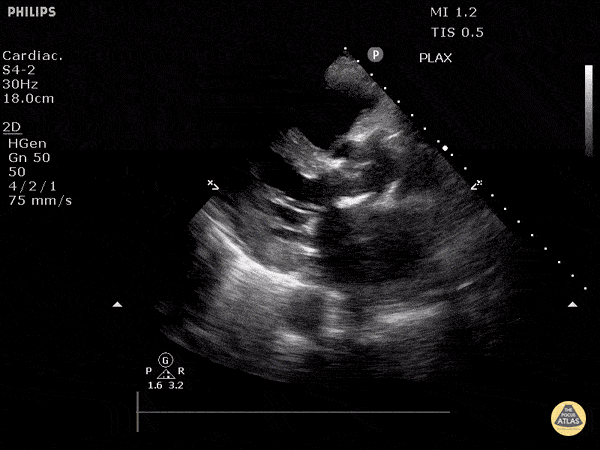

https://www.thepocusatlas.com/valvulopathy

View: Unspecified Parasternal Long Axis Parasternal Short Axis Apical Four-Chamber Subcostal Four-Chamber Subcostal Inferior Vena Cava Right Upper Quadrant Left Upper Quadrant Suprapubic Longitudinal Suprapubic Transverse Subxiphoid Anterior Thoracic Phrenic